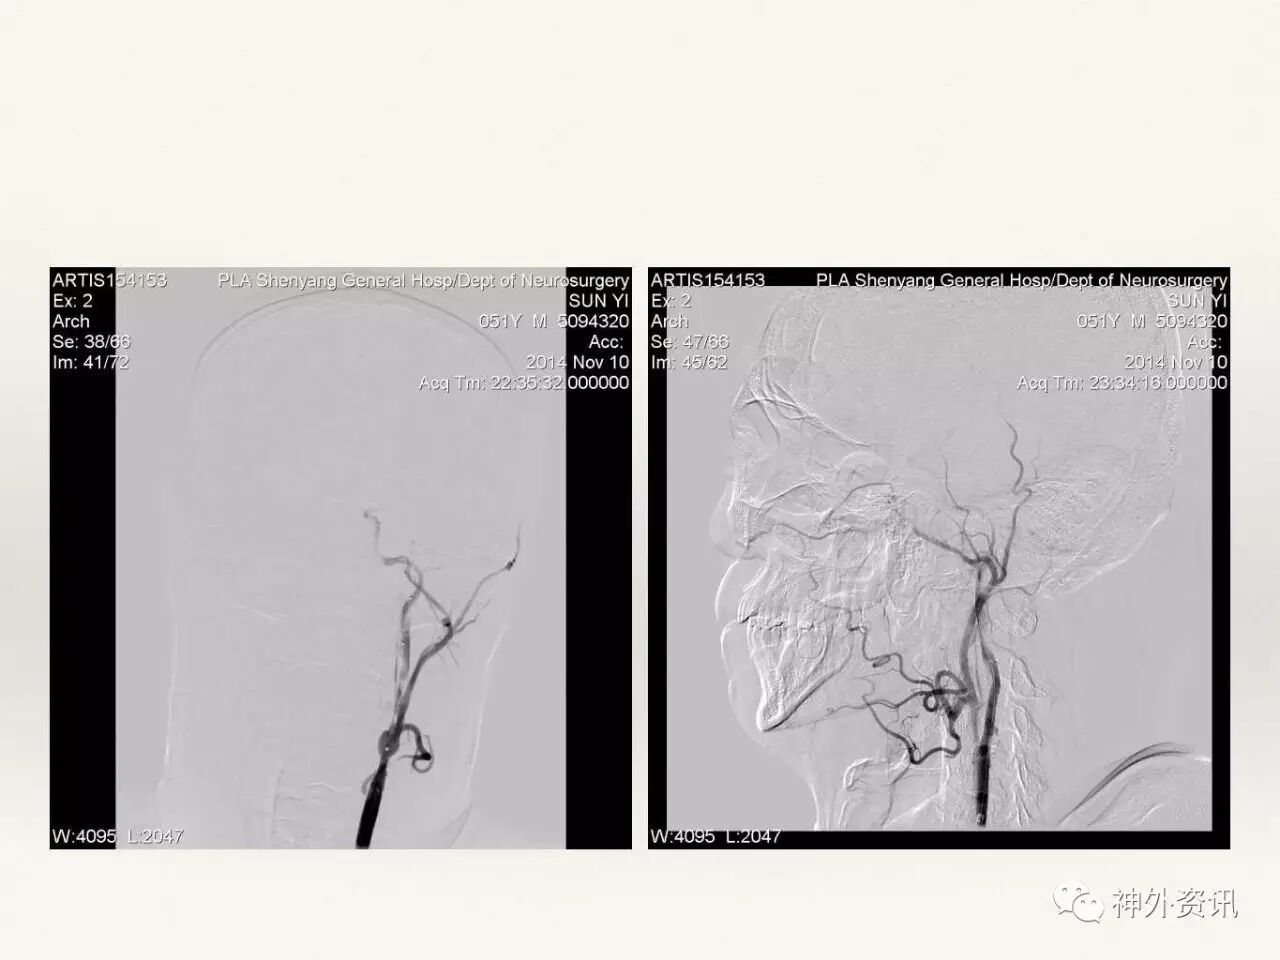

在东北地区率先开展了颈内动脉、大脑中动脉及基底动脉闭塞血管内再通、颅内动脉栓塞急性期取栓、血流导向装置治疗大型宽颈动脉瘤等,对颅内动脉瘤、动静脉畸形、颈动脉及颅内动脉狭窄、颈内动脉海绵窦瘘、硬脑膜动静脉瘘等外科治疗具有较深的造诣。完成脑血管造影8600余例,各类脑血管病介入手术共4500余例,动脉瘤、动静脉畸形、脑肿瘤、脑出血及脑外伤等外科手术1500余例。